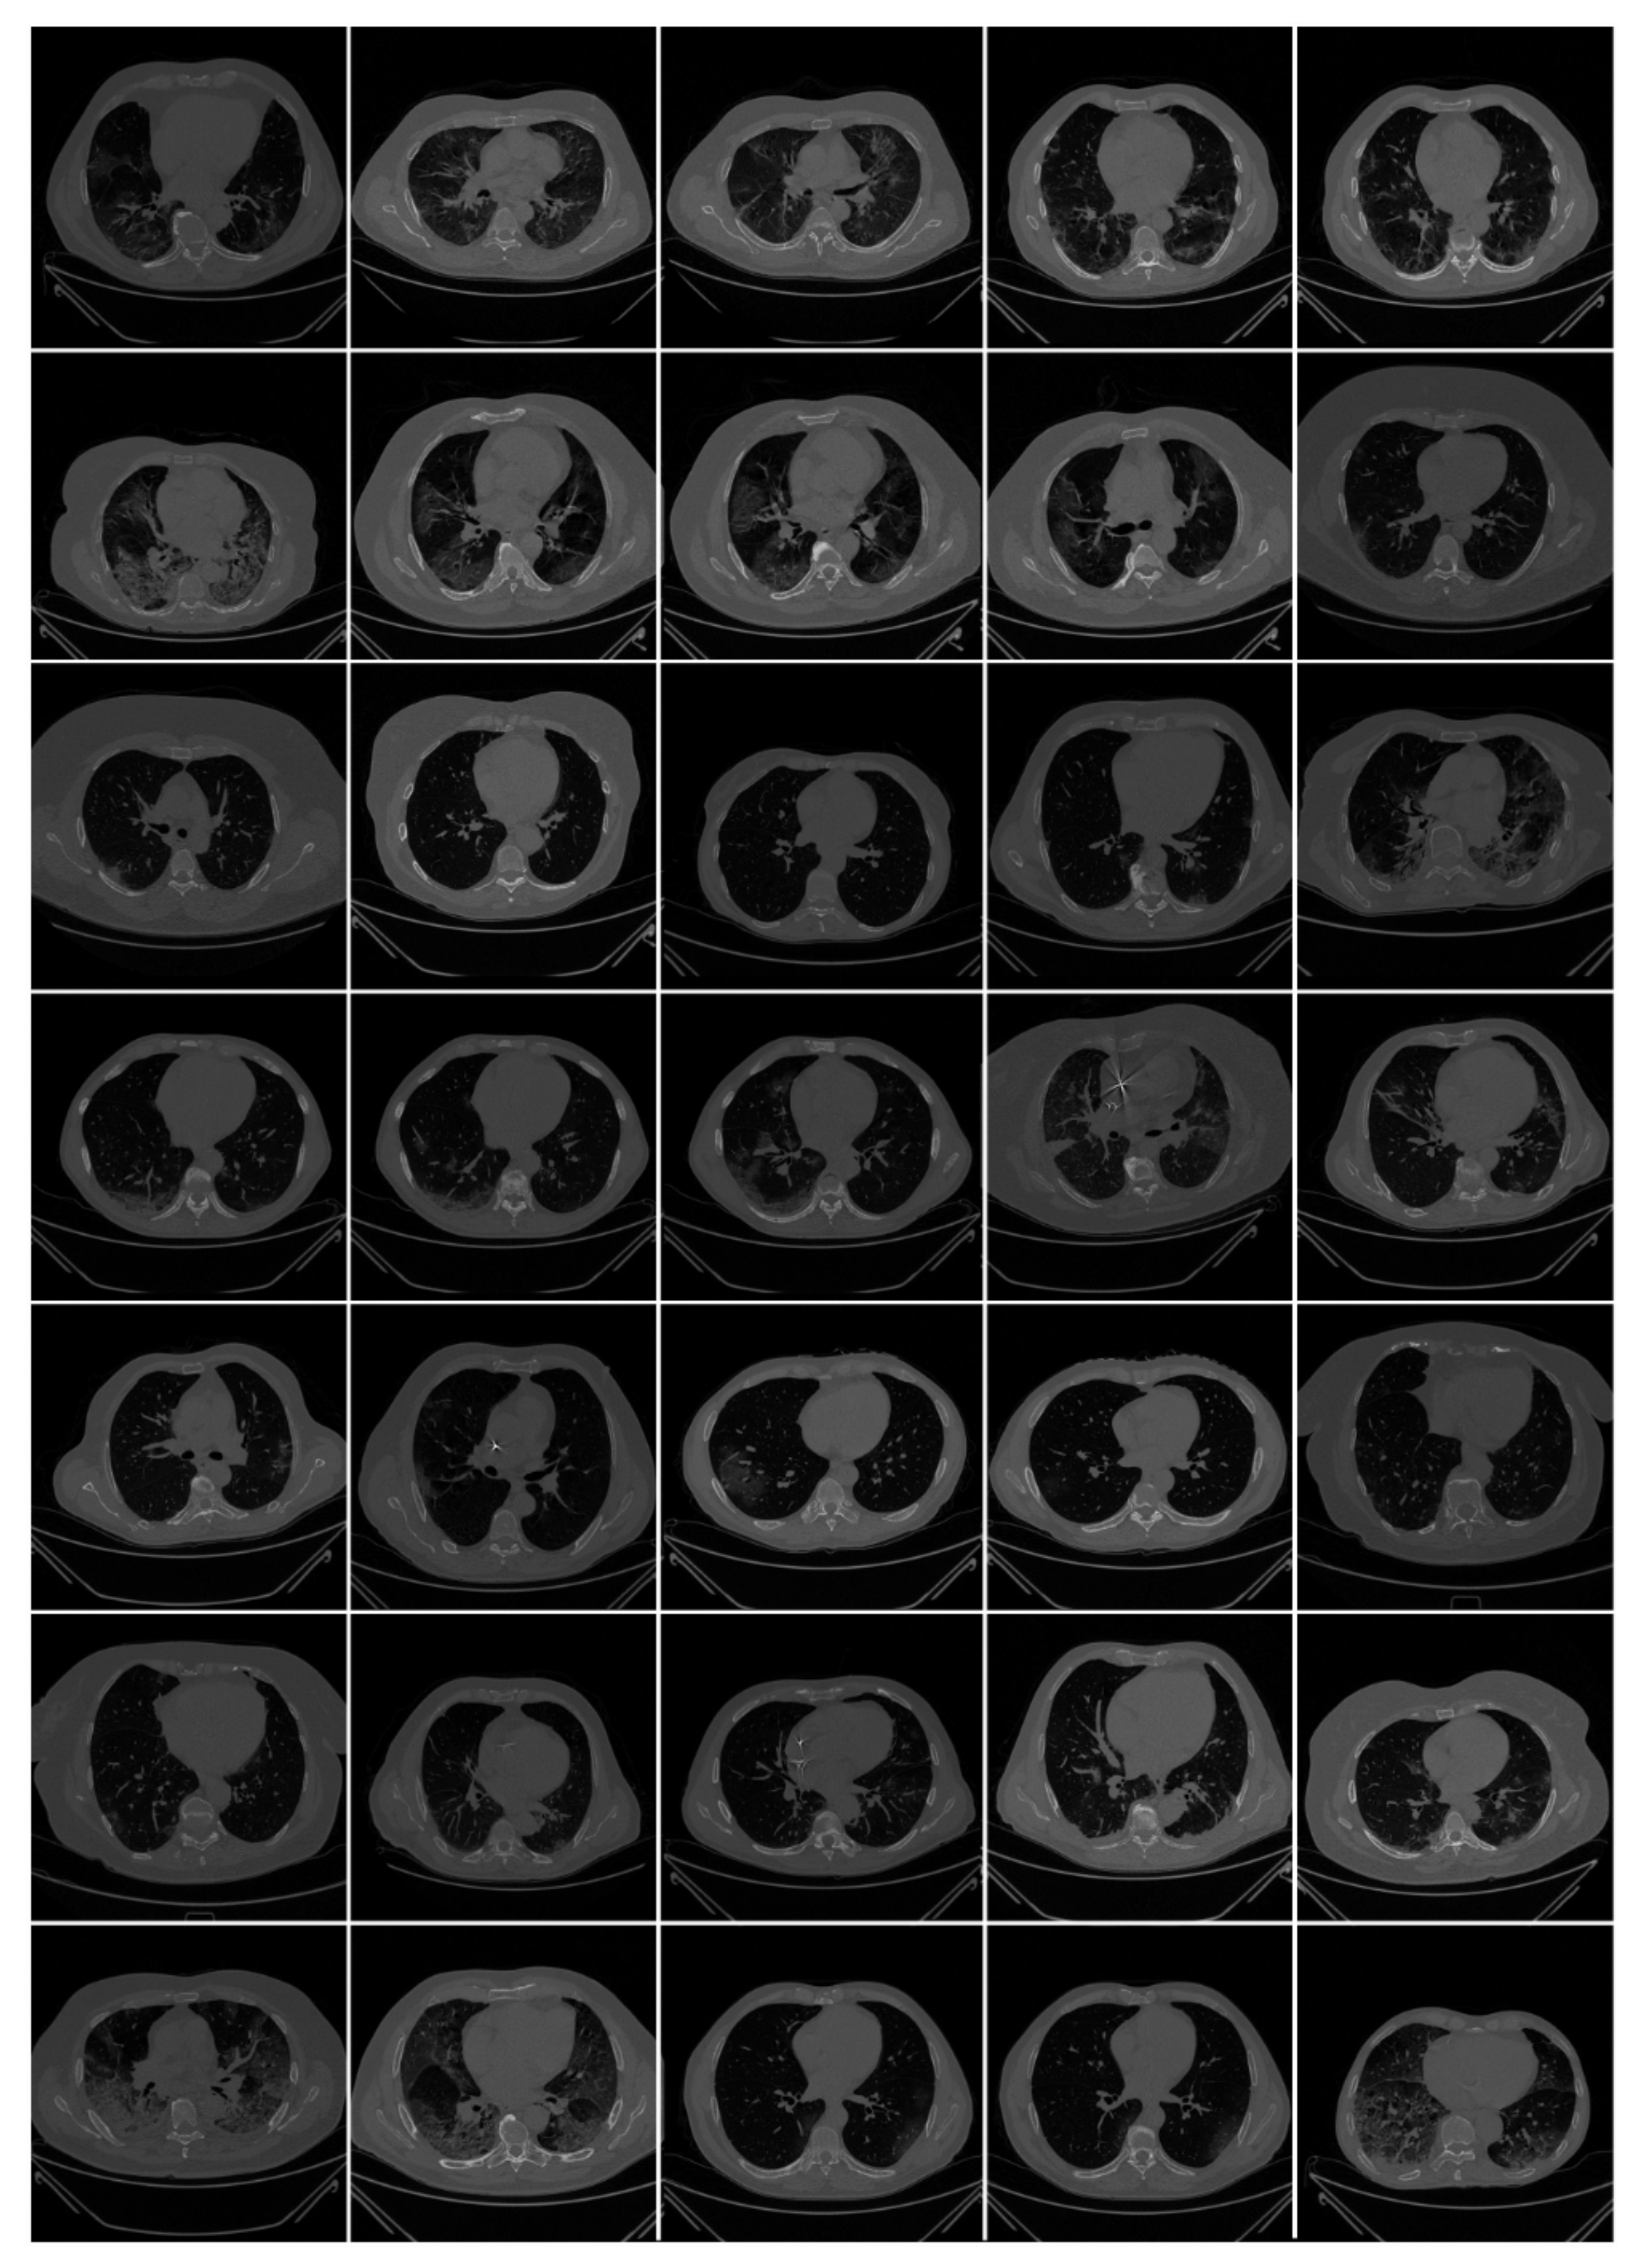

3.1. Material: Patient Demographics and Image Acquisition

3.1.2. Image Acquisition for Italian and Croatian Cohorts

3.1.3. Data Preparation